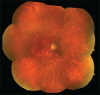

Birdshot retinochoroidopathy (BSRC) is an uncommon, but well-characterized chronic, bilateral posterior uveitis, which is uniquely associated with the human leukocyte antigen-A29 phenotype. The disease presents predominantly in middle-aged Caucasian females who complain of blurred vision, floaters, photopsias, paracentral scotomas and nyctalopia. While autoimmune mechanisms are thought to play an important role in the pathogenesis of BSRC, its etiology remains unknown. Important questions remain in our understanding of BSRC with respect to its pathogenesis, epidemiology, optimal treatment, and prognosis, including the determinants of remission and relapse, as well as the best strategy for monitoring disease activity, progression and response to therapy with electroretinographic and psychophysical testing, established and emerging imaging modalities, and peripheral cytokines profiles.